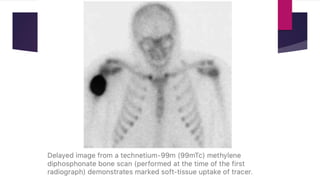

 In the early stages, scintigraphic scan reveals intense uptake at the

site of lesion that reduces in intermediate stages and finally becomes

cold in late stages.

 Approximately 2.5 weeks after injury, flow studies and blood pool

images can detect development of incipient HO.

 Typical findings of delayed scintigrams however become positive one

week later.

 Bone scans are sensitive enough that they can be performed serially

to identify metabolically silent lesions that can be excised.